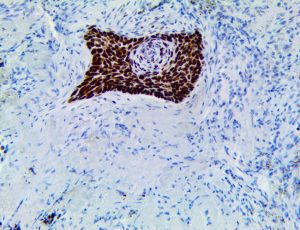

It is the ICU physician who is most likely to witness one of the deadliest manifestations of the abnormal immunological response, the cytokine storm syndrome (CSS). This response is also referred to by some as the cytokine release syndrome (CRS). CSS is characterized by continuous activation and expansion of macrophage and lymphocyte populations, which secrete large amounts of cytokines, causing the cytokine storm. This massive cytokine release is akin to hemophagocytic lymphohistiocytosis (HLH) disease, a syndrome characterized by initial unchecked and persistent activation of cytotoxic T lymphocytes and NK cells.

Clinical and laboratory manifestations of HLH include fever, enlarged liver and/or spleen, neurologic dysfunction, coagulopathy, liver dysfunction, cytopenias (i.e., low levels of erythrocytes, leukocytes, and/or platelets), hypertriglyceridemia, hyperferritinemia, hemophagocytosis, and eventually diminished NK cell activity as the immune system becomes progressively paralyzed. HLH can be familial (primary HLH) or secondary to another disease process (sHLH), such as rheumatic disease, in which it is referred to as macrophage activation syndrome (MAS, characterized by elevated ferritin).